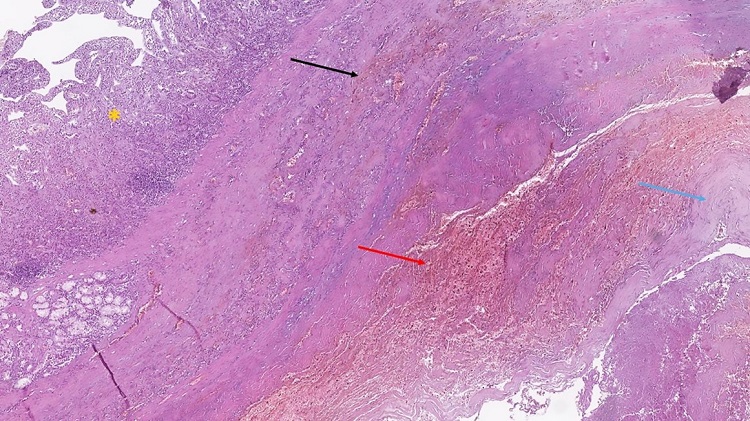

Histopathology of the specimens from the area of the PADF revealed an atherosclerotic nature of the aneurysm, fibrinoid necrosis of the aortic wall, and hemorrhagic changes in the wall and mucosa of the adjacent duodenal wall, without any evidence of duodenal ulcers or ischemic change (Figure 4).